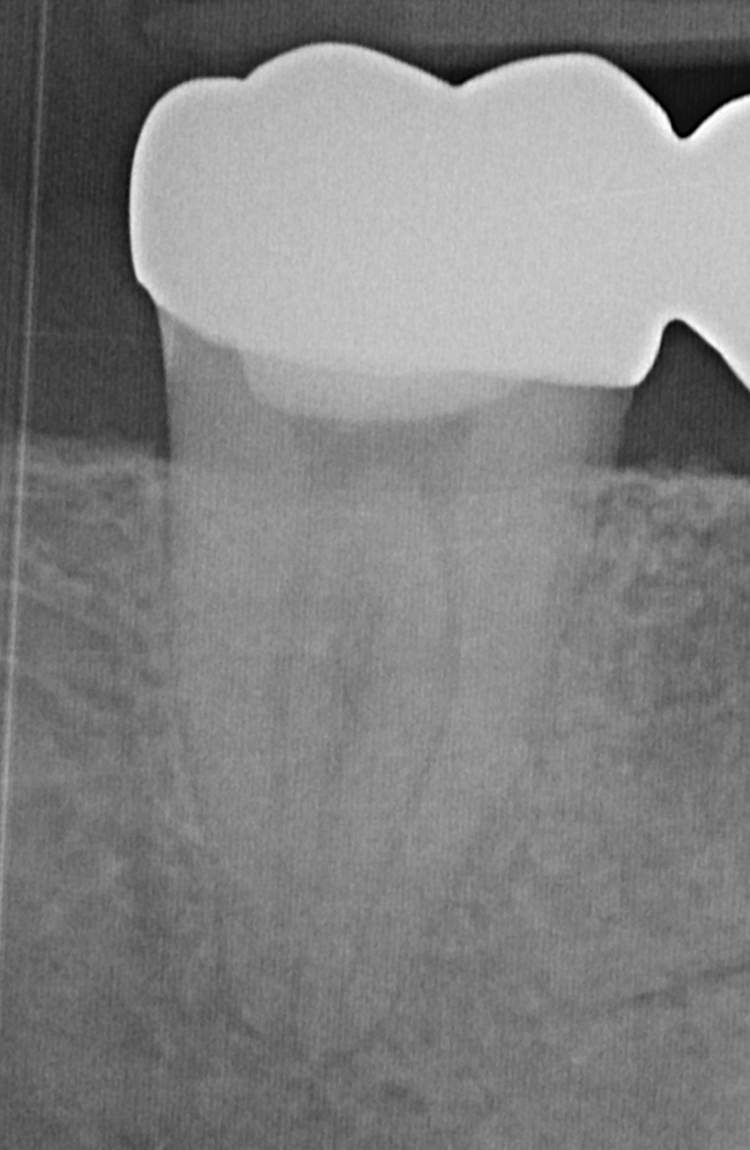

Nachdem das gesamte Kanalsystem steril aufbereitet wurde, erfolgt die Füllung. Um das komplexe anatomische System aus Hohlräumen in allen Dimensionen dicht zu füllen, wird mit einem speziellen Verfahren kautschukartiges biokompatibles Material im Wurzelkanalsystem erhitzt und kompaktiert und so auch in kleinste Hohlräume zu gelangen. Die dichte Füllung des gesamten Hohlraums ist die Grundvoraussetzung zur Vermeidung einer erneuten Bakterienbesiedlung des Zahns.

Nach der Wurzelfüllung erfolgt der dichte Verschluss der Zugangsöffnung mit Kunststoff, um eine erneute Besiedlung durch Bakterien der Mundhöhle zu verhindern.

Die optische Vergrößerung des Mikroskops, in Kombination mit modernsten Aufbereitungs- und Desinfektionstechniken ermöglicht Erfolgsquoten von bis zu 95%, wodurch in vielen Fällen als hoffnungslos geltende Zähne erhalten und so operative Eingriffe wie Wurzelspitzenresektionen und Implantate vermieden werden können.